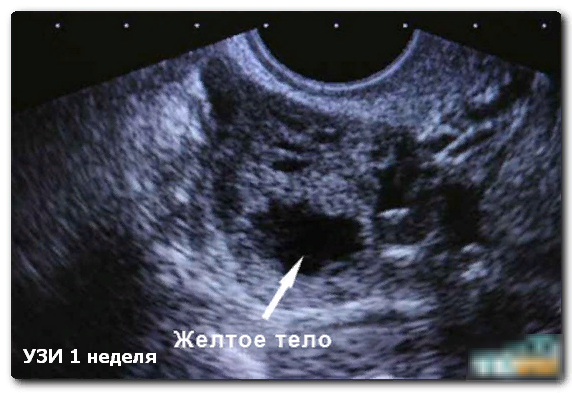

Желтое тело в яичнике: что это такое на УЗИ

Это временное образование на яичнике, как подтверждение того, что прошла нормальная, здоровая овуляция. На УЗИ желтое тело в яичнике? Что это такое, ответит врач-узист. Это подтверждение того, что женский организм способен к деторождению.

Это свидетельствует о наступлении лютеиновой фазы. ЖТ образуется из фолликулярных клеток, на УЗИ его можно увидеть, только если осмотр совпадает с моментом овуляции.

Аппарат УЗИ показывает ЖТ округлым неоднородным образованием. Оно просматривается и когда проводится трансабдоминальное УЗИ, через стенки брюшины. Однако наиболее достоверные результаты получаются на трансвагинальном УЗИ, когда используется внутривагинальный датчик.

Лютеиновая железа обычно визуализируется на одном яичнике. Это свидетельствует о прохождении овуляции, но не о начале беременности. ЖТ дает нормальный фон для зачатия, синтезом гормонов делает вероятным его совершение. Прогестерон начинает готовить эпителий тела матки к укреплению эмбриона. Это значение имеет желтое тело в яичнике, что просматривается на УЗИ, и у врача не возникает вопроса, что это такое.